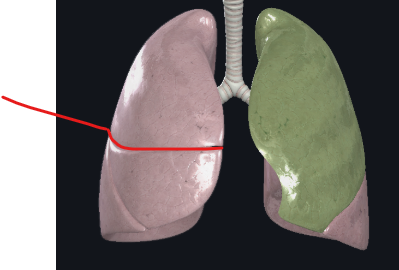

What structure is this?

Cardiac Notch

What structure is this?

Superior lobe of the left lung

What structure is this?

Inferior lobe of the left lung

What structure is this?

Superior Lobe of the right lung

What structure is this?

Middle lobe of the right lung

What structure is this?

Inferior lobe of the right lung

What structure is this?

Left lung

What structure is this?

Right lung

What structure is this?

Horizontal fissure of right lung

What structure is this?

Oblique fissure of right lung

What structure is this?

Oblique fissure of left lung